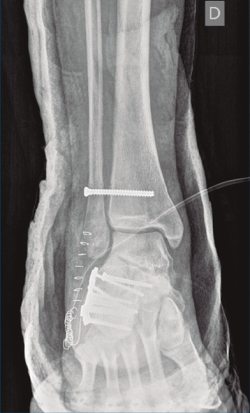

A su llegada a urgencias, se inmovilizó con férula posterior de yeso tras no conseguirse la reducción cerrada (Figuras 7 y 8). Debido a la patología asociada, subsidiaria de tratamiento quirúrgico de urgencias (artrodesis de L2 a L4 con tornillos transpediculares, por parte de neurocirugía), se decide demorar eñ tratamiento definitivo de la fractura luxación de calcáneo 2 semanas, hasta conseguir una mejoría en el estado de las partes blandas.

Figura 7. Radiografía lateral de pie y tobillo; se evidencia fractura de calcáneo y de maléolo tibial posterior.

Figura 8. Radiografía anteroposterior de tobillo, inclinación lateral del astrágalo, ocupación del espacio subperoneo, fractura maléolo peroneo y apertura de sindesmosis.